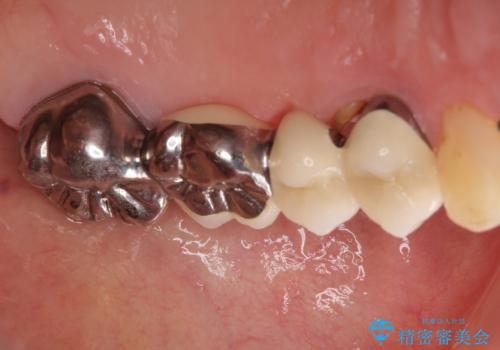

- 上の奥歯に装着されているブリッジが痛むとのことで来院された患者様です。

診察した結果、ブリッジの土台となっている歯が割れていたため、抜歯が必要となりました。

欠損している歯数が多いため、ブリッジによる補綴治療は困難と判断し、インプラントによる補綴治療を行うこととしました。